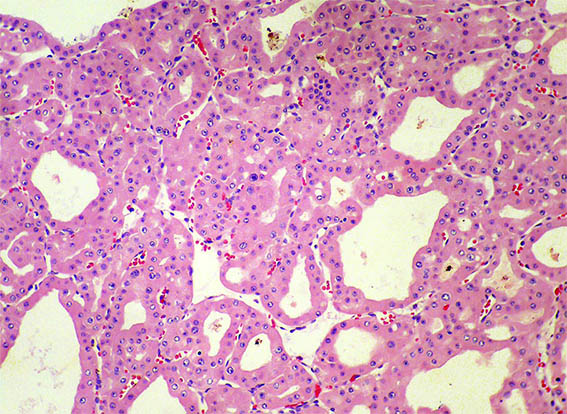

Figure 5. H&E, X100.